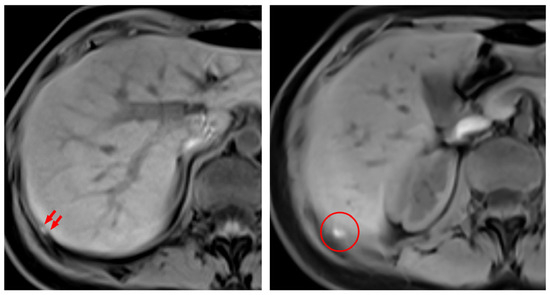

- Rousset, P.; Gregory, J.; Rousset-Jablonski, C.; Hugon-Rodin, J.; Regnard, J.F.; Chapron, C.; Coste, J.; Golfier, F.; Revel, M.P. MR diagnosis of diaphragmatic endometriosis. Eur. Radiol. 2016, 26, 3968–3977. [Google Scholar] [CrossRef] [PubMed]